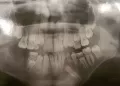

При осмотре КТ справа по доразально медиальной стенке, на уровне корня 15 зуба, определяется образование с неоднородной плотностью содержимым, от 27-40 едХ, с выпуклым контуром, с наличием кальцинированной капсулы, размером 30Х16Х25 мм.

Заключение: Киста правой ВЧП.